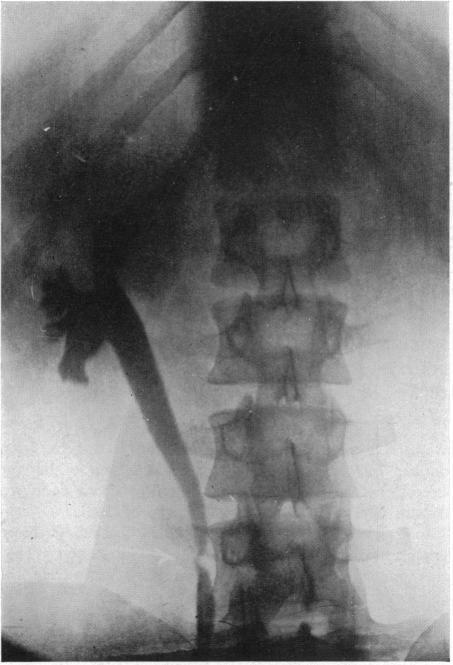

STRICTURE OF THE URETER.

Ann Surg. 1925 Apr;81(4):839-50. doi: 10.1097/00000658-192504000-00013.